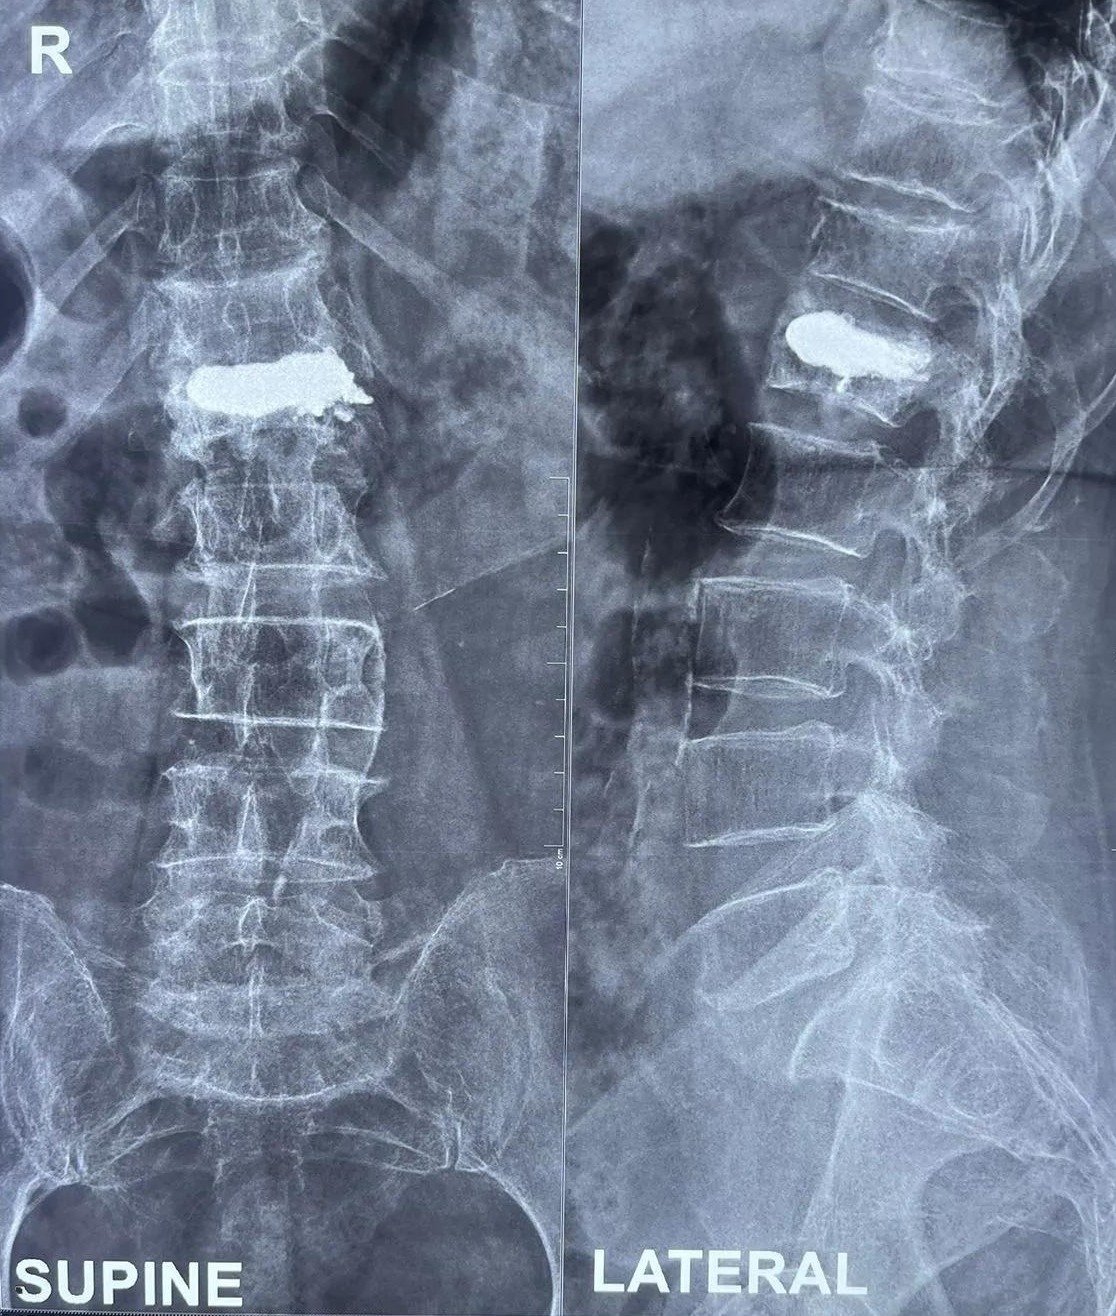

Vertebroplasty is a minimally invasive surgical procedure designed to stabilize spinal fractures and relieve pain caused by vertebral compression fractures. These fractures are often due to osteoporosis, cancer, or spinal injuries. The procedure involves injecting a special medical-grade cement into the fractured vertebra to provide stability and reduce pain.

Consultation and Evaluation: Before recommending vertebroplasty, our specialists conduct a thorough evaluation, including a detailed medical history, physical examination, and imaging studies such as X-rays, CT scans, or MRI.